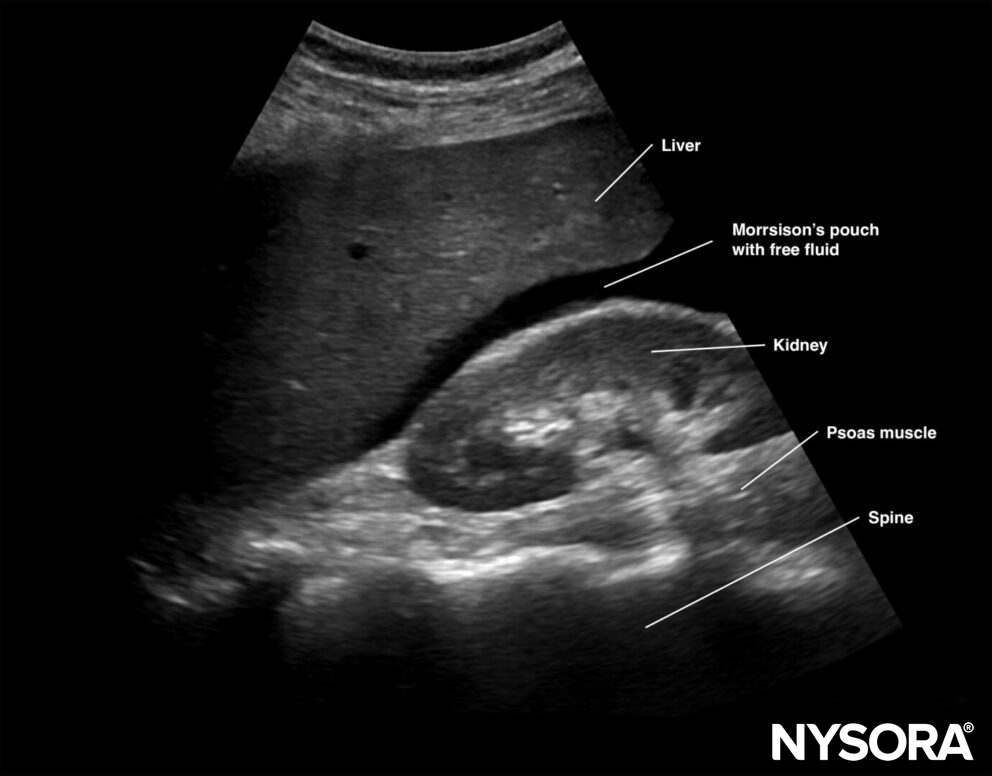

Free intraperitoneal fluid:

Free right intraperitoneal fluid collects between the liver and the kidney (Morrison’s pouch). If intrathoracic free fluid is present, it can be identified above the diaphragm.

Free intraperitoneal fluid is often found between the liver and the kidney, i.e., Morrison’s pouch.